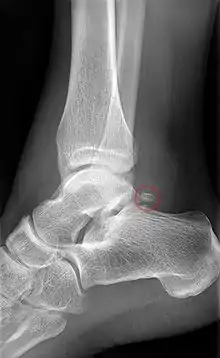

Ankle

Accessory bones of the ankle.[13]

Accessory bones at the ankle mainly include:

• Os subtibiale, with a prevalence of approximately 1%.[14] It is a secondary ossification center of the distal tibia that appears during the first year of life, and which in most people fuses with the shaft at approximately 15 years in females and approximately 17 years in males.[14]

• Os subfibulare, with a prevalence of approximately 0.2%.[15]

Os trigonum (further described below) may also be seen on an ankle X-ray.

Os trigonum

The os trigonum or accessory talus represents a failure of fusion of the lateral tubercle of the posterior process of the talus bone. Is estimated to be present in 7–25% of adults.[17] It can be mistaken for an avulsion fracture of lateral tubercle of talus (Shepherd fracture) or a fracture of the Stieda process. In most cases, Os Trigonum will go unnoticed, but with some ankle injuries it can get trapped between the heel and ankle bones which irritates the surrounding structures, leading to Os Trigonum Syndrome.[21]